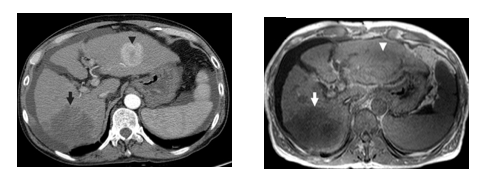

For the medical imaging technique, two relevant options are discussed: Computer Tomography (CT) and Magnetic Resonance Imaging (MRI).

On the one hand, a CT scan (Figure 16, left) creates a cross sectional, 3D image of the body. The scan gives detailed pictures of the tumour(s) and surrounding tissues and organs, enabling the doctors treating you to gain an accurate picture of the tumour, and its location. On the other hand, MRI (figure 16, right) uses magnetic and radio waves (not X-rays) to show the tumour(s) in great detail and look at the blood supply to the liver. Also, for both CT and MRI, the patient may be given an injection of a contrast medium during the scan in order to produce a better image [32].

| Figure 16. Medical imaging techniques applied to the abdominal field (axial view): CT (left) and MRI (right) [29] |